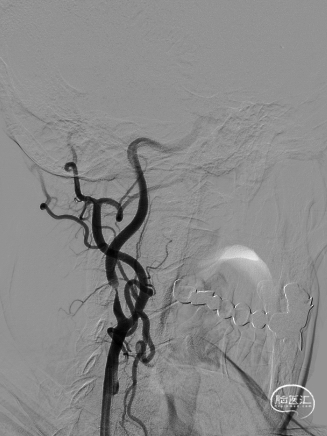

保护伞到位后释放(左图箭头),2.5*20mm通桥白驹®球囊以6atm扩张(右图箭头)。